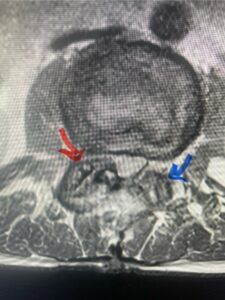

Another patient, a 77 year-old female, presents with pain, numbness, and weakness of her arms and difficulty with balance over a 6-month period. MRI revealed severe osteophytic disease at C5-C7 with cord compression (Fig. 4). Further work-up by fine-cut cervical CT to evaluate the nature of compression revealed a completely calcified osteophyte (Fig. 5). Although the patient had a good lordosis and a posterior cervical approach would accomplish an adequate decompression, we elected to perform a two-level anterior cervical discectomy and fusion. This particular osteophyte is formidable because of its size but the compression was all anterior and would be a less invasive approach. Fortunately, during the procedure, the patient had a fair amount of osteoporosis which allowed the osteophyte to be drilled and bit away with considerable ease. Interestingly, the C6 7 osteophyte which was more a sheet of osteophyte was more challenging to remove. In the end the decompression went well, and we placed two interbody devices filled with bone graft with plates at each level (Fig. 6). The patient had a nice recovery with immediate reduction of pain and numbness. This case demonstrates the importance of recognition of cervical myelopathy in its early stages. A significant reversal of function is generally the rule if the patient has appropriate correlative findings on exam and MRI, particularly with long tract distribution weakness development within a year time period.

Figs 4a: Sagittal and axial T2-weighted cervical MRIs demonstrating large osteophyte worse at C5-6 compressing spinal cord more eccentrically to the left (red arrows)